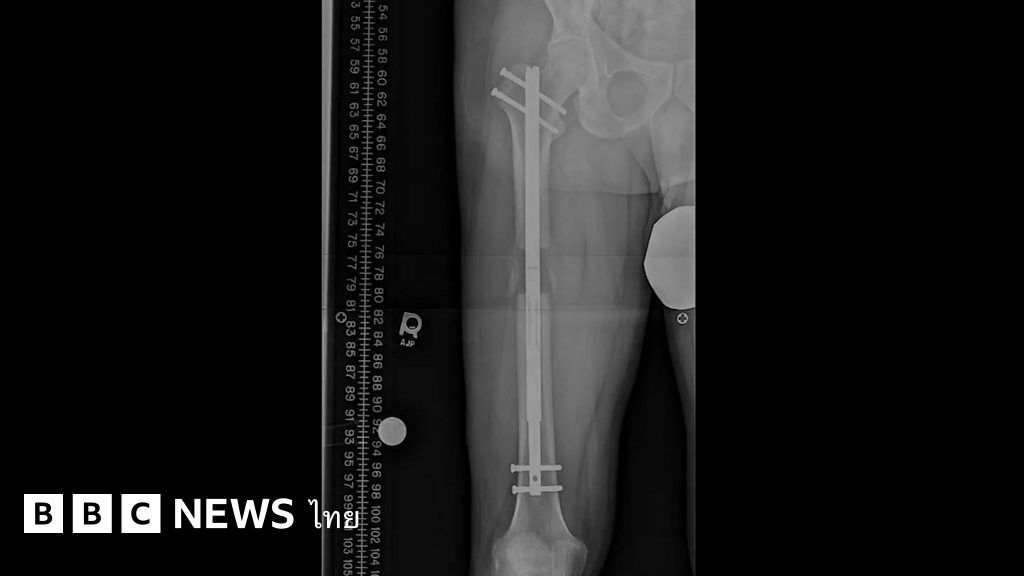

การผ่าตัดเพิ่มความยาวขา เป็นกระบวนการที่ยุ่งยากซึ่งต้องมีการฝังหมุดยึดลงไปในกระดูกขา และค่อย ๆ ขยายหมุดนั้นเพื่อให้คนไข้ค่อย ๆ สูงขึ้นได้มากถึง 13 เซนติเมตร การผ่าตัดเช่นนี้แต่เดิมทำให้แก่เฉพาะคนที่ได้รับบาดเจ็บ หรือไม่ก็มีอวัยวะผิดรูป แต่ปัจจุบัน คนหลายร้อยคนในแต่ละปีเข้ารับการผ่าตัดนี้เพื่อความสวยงามตามคลินิกเอกชนต่าง ๆ ทั่วโลก

การผ่าตัดเพิ่มความยาวขามีราคาสูง ต้องใช้เวลา และมีความเจ็บปวดอย่างมาก อาจจะมีอาการแทรกซ้อนตามมาหลายอย่างได้ แต่ผู้คนจำนวนมากก็เต็มใจที่จะรับความเสี่ยงนั้น